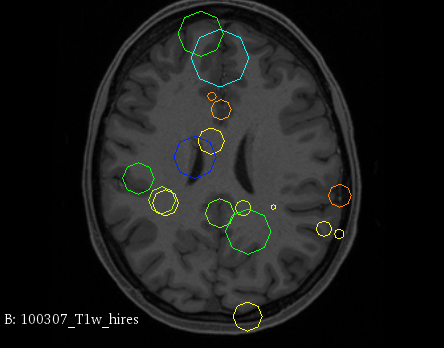

Figure 3 provides a scale-space visualization of feature matches for a single pair of MZ twins and NT siblings, where scale information is represented using the circle radius. Note that circles represent the intersection of 3D spheres with the visible slice and, thus, non-intersecting features are hidden in this 2D visualization.

It can be seen that different image modalities generally result in distinct, complementary feature correspondences throughout the brain, allowing a rich characterization of both anatomical and connectivity structure. In T1 and T2 images, features are mainly located in the frontal lobe, corpus callosum and brain stem. Smaller-scale features are also visible along various cortical regions, as well as in sub-cortical structures near the basal ganglia. Although highly correlated, T1 images show significantly more feature matches than T2 images. Moreover, images based on diffusion measures have less matches than in structural modalities. These matches are located mostly inside or near to white matter: larger-scale features in the corpus-callosum, and smaller-scale ones in the brain stem and along white matter bundles. While not shown in the figure, the set of matches found by combining two modalities (e.g., T1 + T2) generally corresponds to the union of those obtained with these individual modalities.

Comparing different sibling types, we observe a greater number of matches between MZ twins than NT siblings. This observation, which is easier to visualize in T2 and GFA images, is consistent with other analyses on twin datasets. In terms of feature location and scale, no obvious pattern can be seen when comparing these two sibling types. However, a more detailed analysis would be required to validate this assertion.